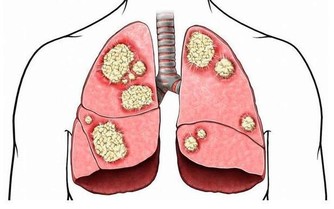

痛風,幾乎也是讓大家聞之色變的一類疾病了,因為一旦患上了痛風,不僅身體會長時間受到折磨,精神上也會感到十分痛苦,而且在痛風患者的日常生活中,稍有不慎就可能會導致其他病症一齊發作。

所以,對於痛風,大家一定要有相關的防範意識,不要等到疾病纏身了,才知道後悔,尤其是平時在飲食中經常攝入高嘌呤食物,且尿酸水平持續偏高的人,更是要注意預防。